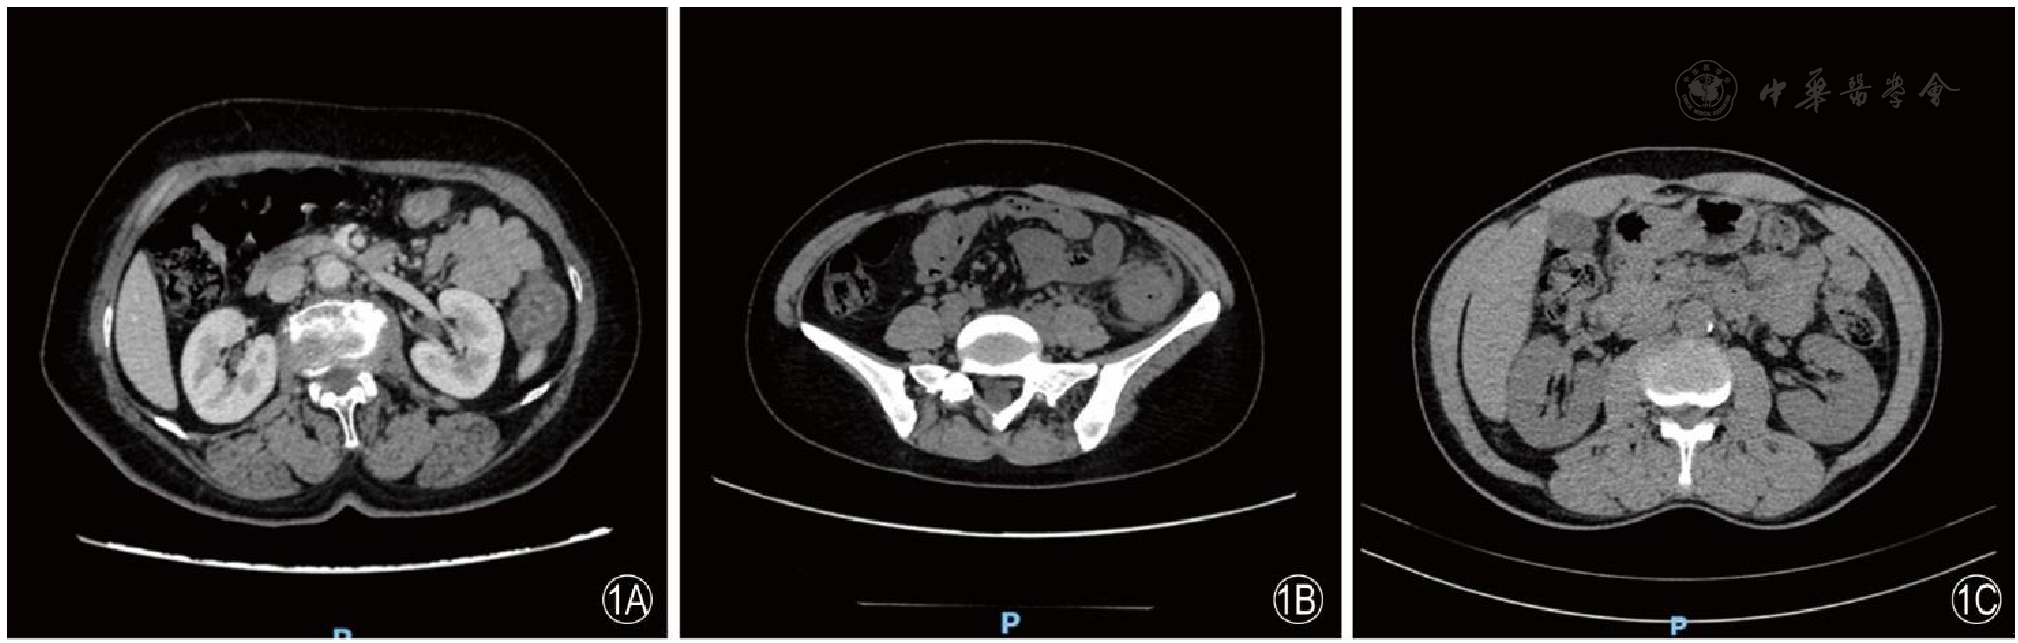

图1 缺血性肠病患者的CT血管成像注:1A降结肠壁增厚,密度减低,增强后强化呈相对低密度,周围间隙模糊;1B降结肠管壁增厚;1C结肠管壁弥漫性增厚